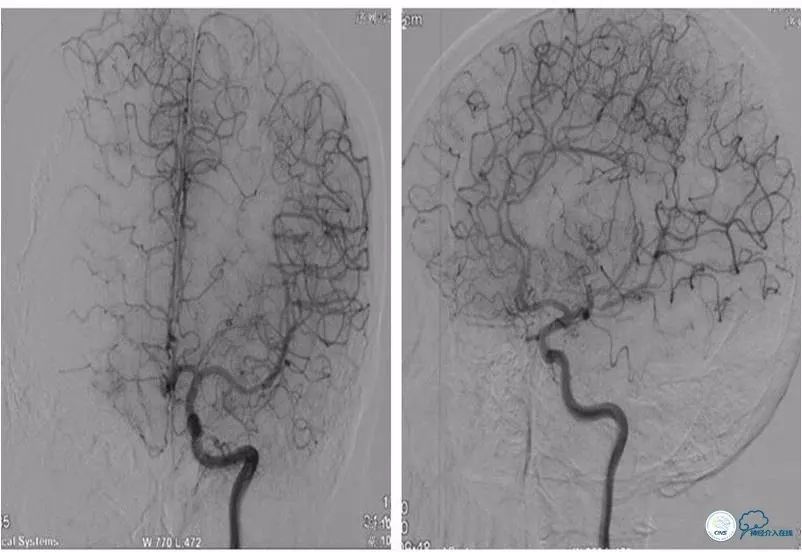

全麻下右股动脉入路,将6F导引导管放至右颈内动脉C1段远端,造影示右颈内动脉C7段重度狭窄(图6)。

图6

路径图下将Transend微导丝(0.014″,300cm)至右大脑中动脉M3段,沿微导丝送入Gateway球囊(2.0mm×15mm)于狭窄处扩张(图7)。

图7

撤出球囊导管,后沿微导丝送入Wingspan自膨式支架(3.0mm×15mm),期间将导引导管送至右颈内动脉C3段,以增加系统支撑力(图8)。

图8

支架释放后造影提示支架贴壁良好,前向血流TICI 3级,脉络膜前动脉未受影响(图9)。

图9